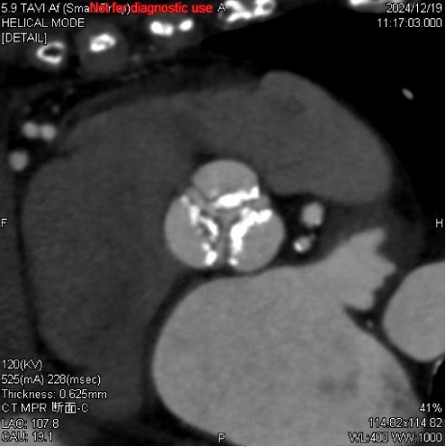

TAVI術前検査における活用例

下記の画像は、TAVI術前検査のAf症例ですが、このデータでも不整脈や石灰化があるにも関わらず弁に対して十分な画像が得られており、列数の影響を感じさせない画像が提供することができました。

循環器医師からも、「64列装置でも十分評価できているね!」と言っていただけるほど、評価が高かったことが印象的です。

Ascend_ayase04.jpgTAVI術前検査でのSSF2.0処理後の画像